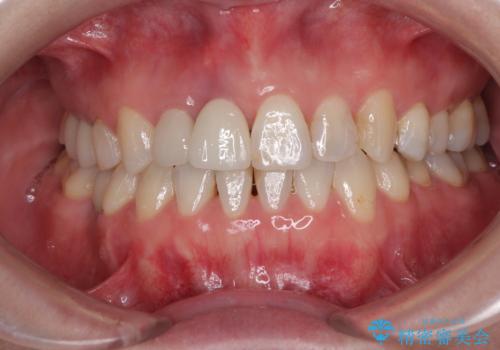

- 前歯のセラミッククランが外れてしまったとのことで来院された患者様です。

診察をしたところ、歯根に縦破折が認められ、抜歯が必要と判断されました。

抜歯、インプラント埋入、仮歯の装着が同時に可能な1DAYインプラントが適用可能と判断されたため、インプラントによる補綴治療を行うこととしました。